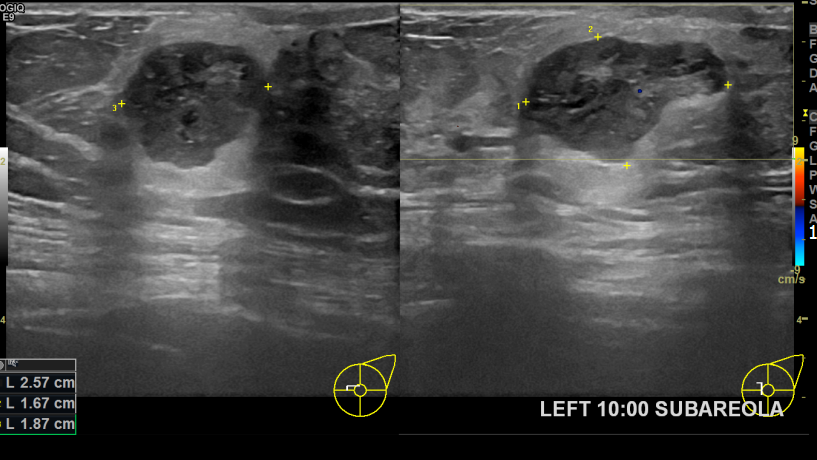

아산유외과개원후 735번째 유방암진단

상기환자 좌측 유방멍울 있어 내원하신 60대 여성분으로 좌측유방멍울 조직검사시행후 유방암 진단되었습니다.